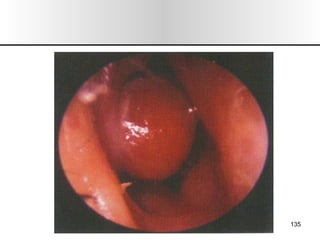

• 2.

• 3.